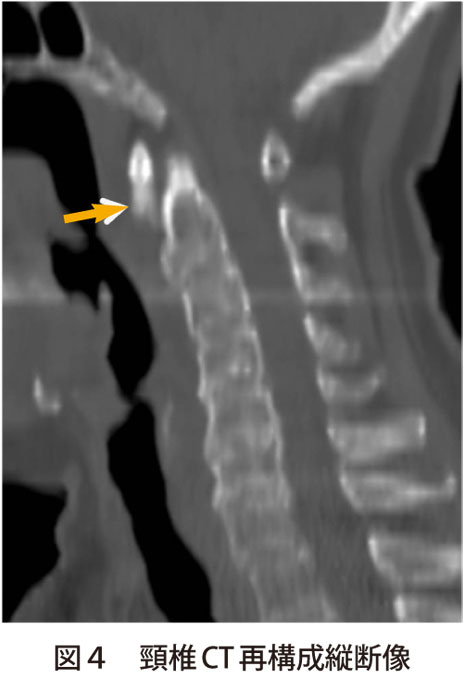

⭕石灰沈着性頸長筋腱炎:

頸長筋膜へのCa塩の沈着で起こる結晶誘発性の炎症。20〜50歳に好発。急性の後頚部痛・頸部運動制限・嚥下痛が出現。採血で炎症反応上昇あり咽後膿瘍や化膿性脊椎炎などとの鑑別が大事。CTで第1〜第2頚椎前面の頸長筋付着部に石灰化像出現。MRIで咽頭後壁の頸長筋に一致する部位の腫脹や浮腫。液体貯留。治療はNSAIDs・安静。重症例はステロイド。